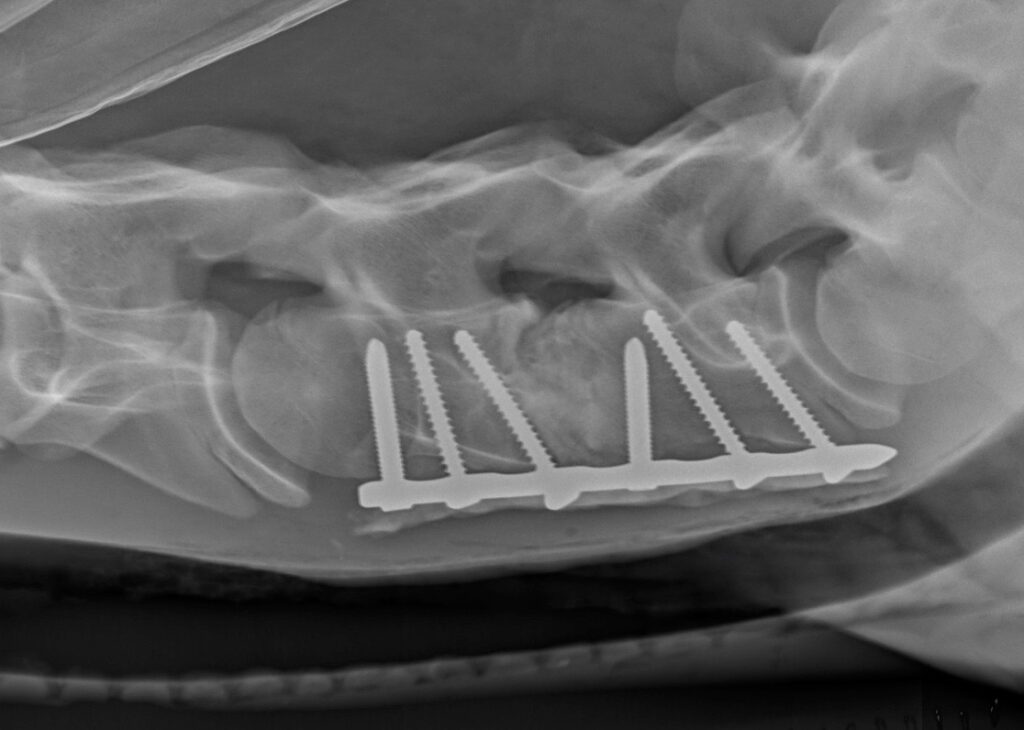

Chirurgické řešení Wobblerova syndromu je jedna ze specialit šéfchirurga Equitomu, dr. Toma Mariëna. Zákrok provádí už od roku 1996, kdy úzce spolupracoval s dr. Barrie Grantem z USA. Koně přijíždějí na kliniku Equitom z celé Evropy, aby podstoupili tuto operaci, a úspěšně vyléčeno už jich bylo několik stovek. Principem zákroku je odstranění nadměrného tlaku na míchu a stabilizace obratlů v jejich přirozené pozici (obr. 9).

Obrázek 9: Kůň na obr. 4 byl vyléčen pomocí dvojité artrodézy (C5–C6 a C6–C7)

Stabilizace je dosaženo umístěním protézy, díky které se dva sousedící obratle spojí. Tímto způsobem dojde k artrodéze (srůstu) nestabilních obratlů, a tlak na míchu se zmírní. Dokonce i u artrózy meziobratlových kloubů dochází po srůstu obratlů ke zmenšení zduřelých obratlových plošek a tím ke snížení tlaku na míchu.

Relativně malý, asi patnácticentimetrový řez se provádí ve spodní části krku (obr. 10) v úrovni problematického místa. Průdušnice a svaly jsou odtaženy stranou a přístup ke krčním obratlům je uvolněn (obr. 11). Titanová protéza je umístěna pod rentgenologickou kontrolou tak, aby dokonale stabilizovala oba obratle (obr. 12). Pokud se vyskytuje více míst, kde dochází ke zvýšení tlaku na míchu, je možné spojit i více obratlů (obr. 9). Tento chirurgický zákrok je v Equitomu zcela běžný a zabere přibližně jeden a půl hodiny (obr. 13).